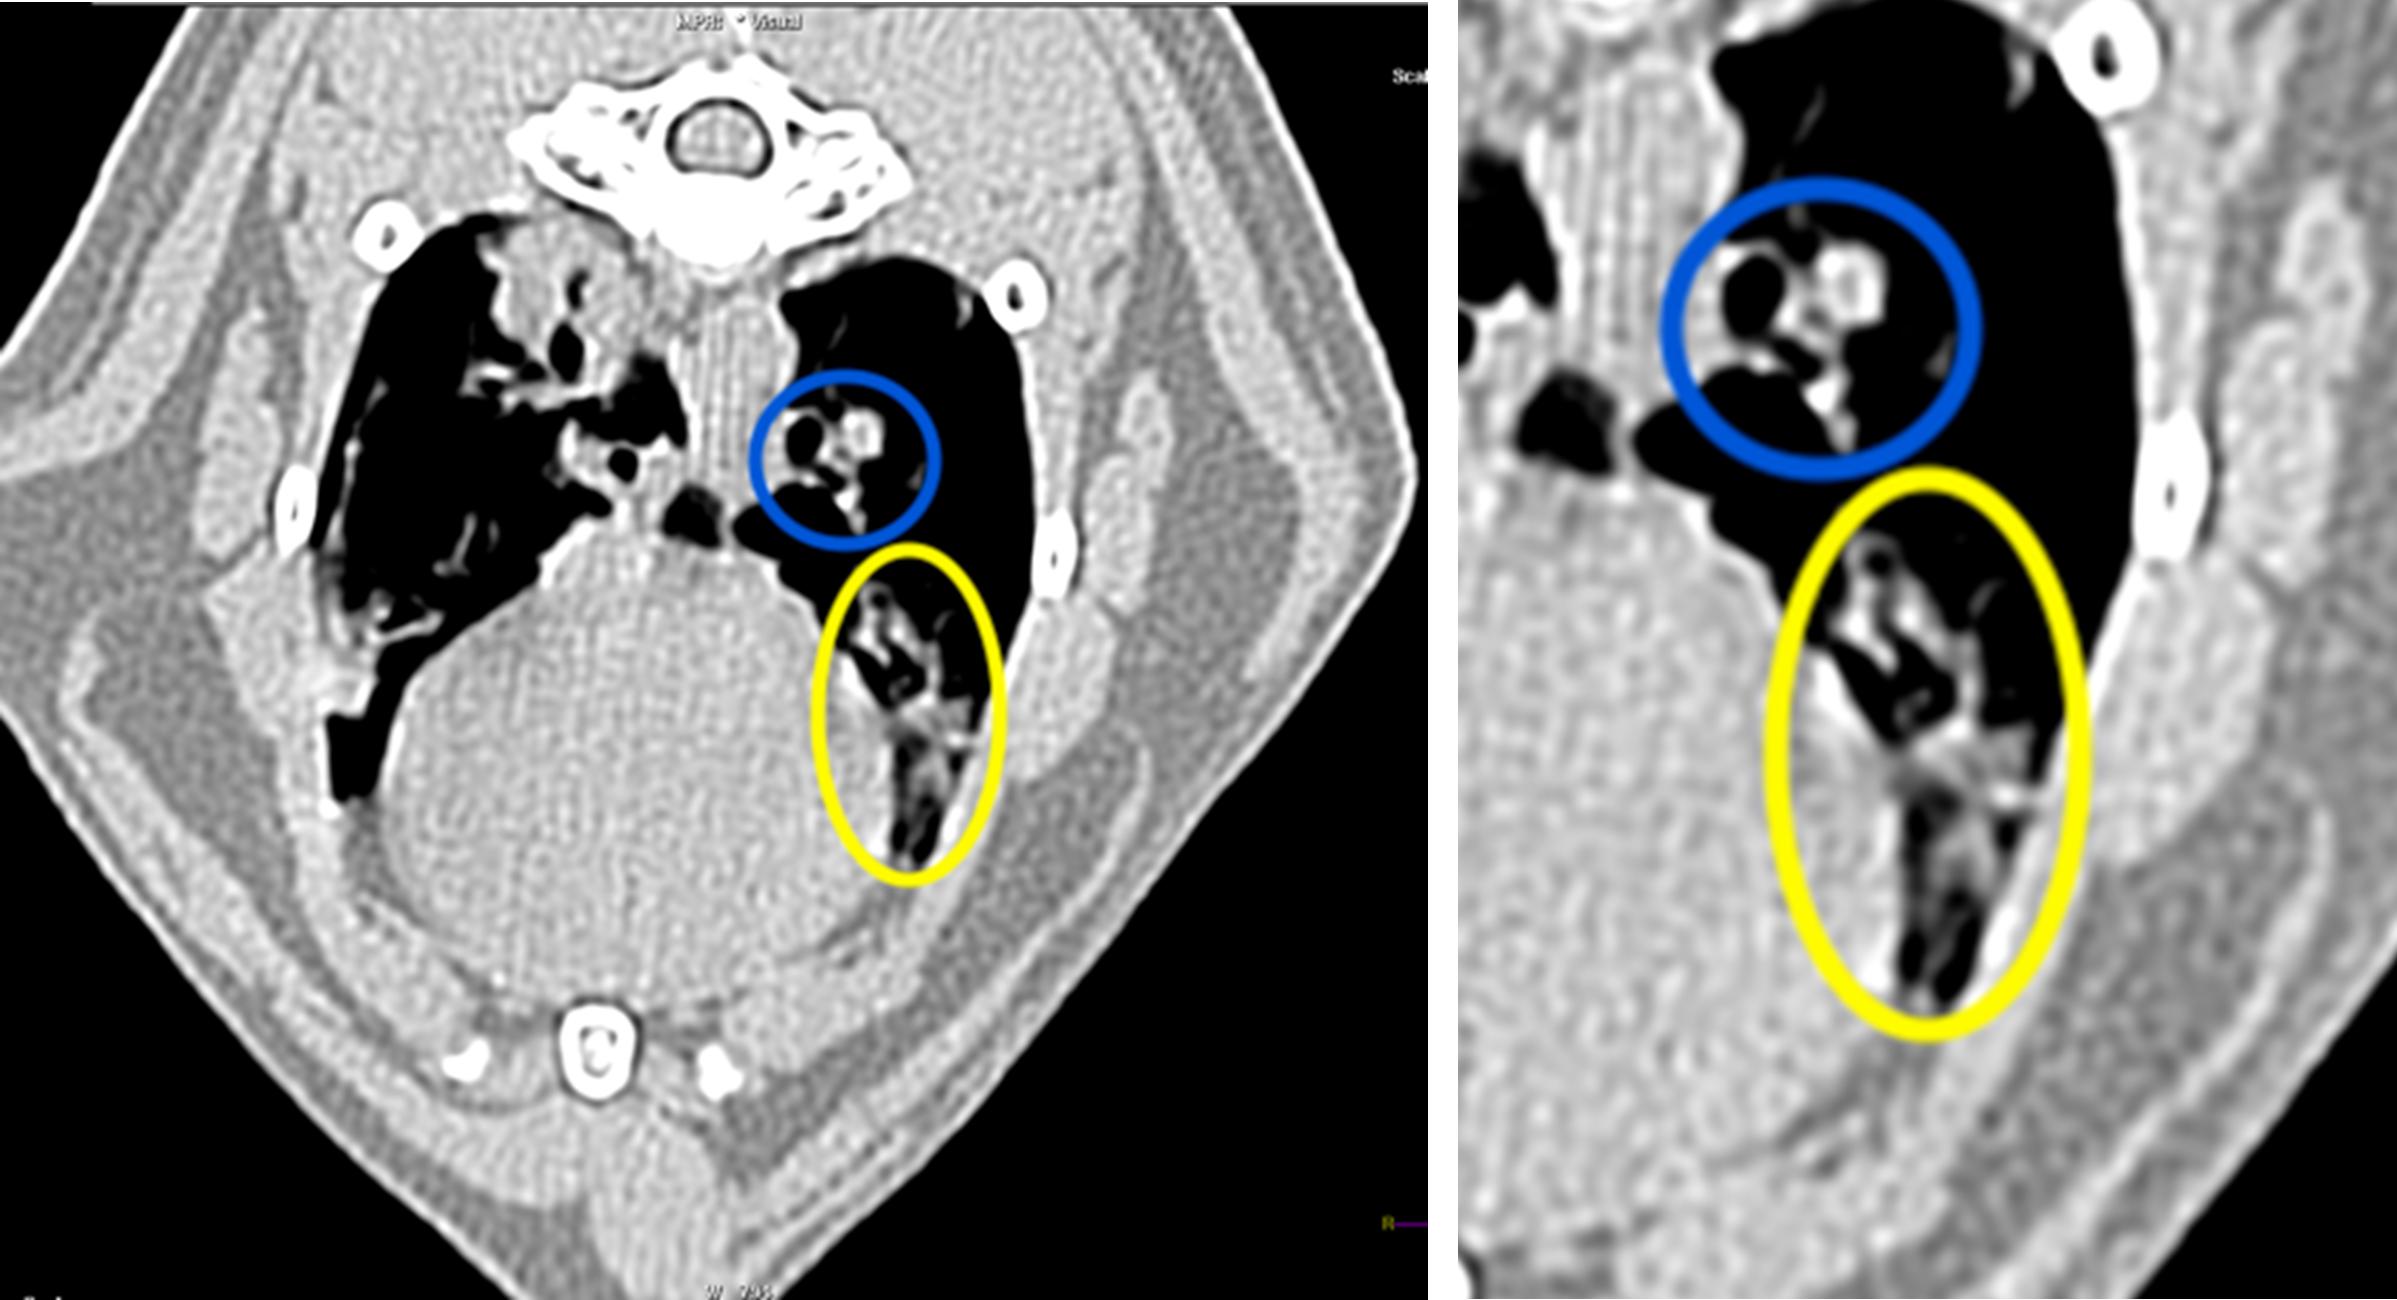

An axial CT image of the thorax is included above, along with a zoomed-in image of the area of interest. The patient’s left is to the right of the image. Several mildly dilated bronchi partially or completely filled with soft tissue attenuating material are in the left cranial lung lobe (circled in blue and yellow). The affected bronchi are branching with areas of rounded peripheral margination, creating a “tree-in-bud” appearance. The walls of these bronchi display diffuse or multifocal pinpoint hyperattenuating regions, consistent with mineralization. Additional changes not shown on the provided images include mild diffuse bronchial wall thickening throughout all lung lobes and a few smaller isolated soft tissue attenuating nodular foci associated with peripheral bronchi in other lung lobes. The isolated lesions were not seen radiographically. The patchy, soft-tissue- and gas-attenuating regions in the included right lung lobes are consistent with recumbency atelectasis and hypoinflation resulting from sedation. As suspected radiographically, lower airway disease with multilobar mucus plugging was prioritized with concurrent bronchiolithiasis/dystrophic mineralization of the peribronchial glands.